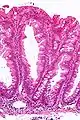

La partie profonde des glandes est souvent élargie, a tendance à se diviser en deux ou trois branches et à s’horizontaliser, c'est-à-dire à se disposer parallèlement à la musculaire muqueuse et non pas perpendiculairement à elle, comme dans les polypes hyperplasiques conventionnels et les adénomes festonnés traditionnels.